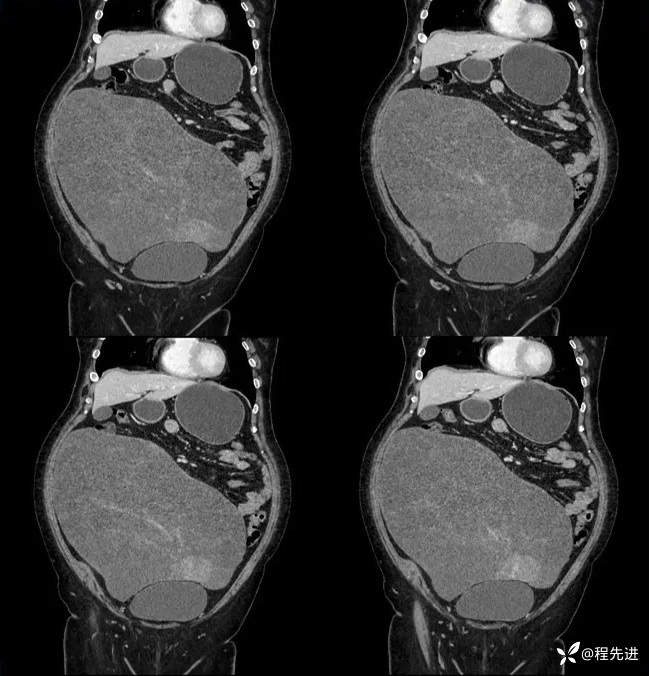

平扫:

动脉期: